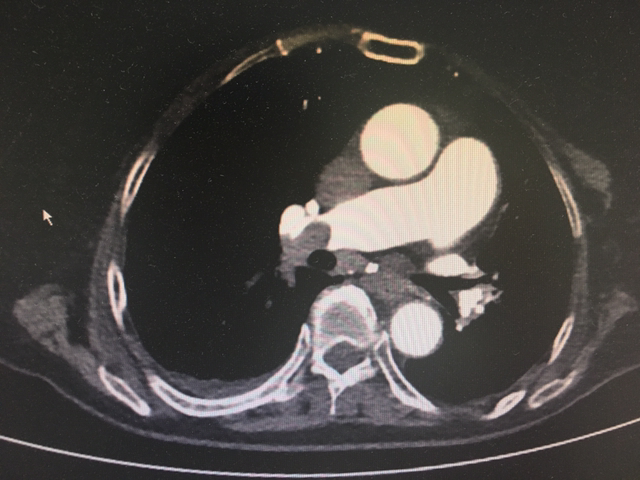

앗, 심장 뛰는 게 심상치 않다. 심증에 힘 실어줄 단서를 기대하며 흉부 CT까지 살핀다. 역시나 PTE (pulmonary thromboembolism, 폐동맥 색전증).

흉부 CT 상 PTE. 페동맥 색전증이 자명하다.

허파 우상엽에 mass. 종양에 의한 PTE로구나.